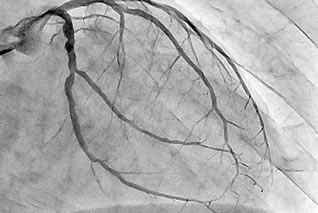

で、目の前にモニターがあって良く見えるんですよ。

造影剤を飲んで心臓の形がはっきり映し出されます。

・・・おお、なかなか綺麗ですね。

とまあ一応ほめていただきましたよ。